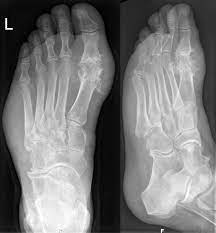

- X선 검사: 관절 및 주변 조직의 염증, 결정의 쌓임 정도를 평가하기 위해 X선 검사를 사용할 수 있습니다. 하지만 통풍의 초기 단계에서는 X선상으로는 볼 수 없는 경우가 많습니다.